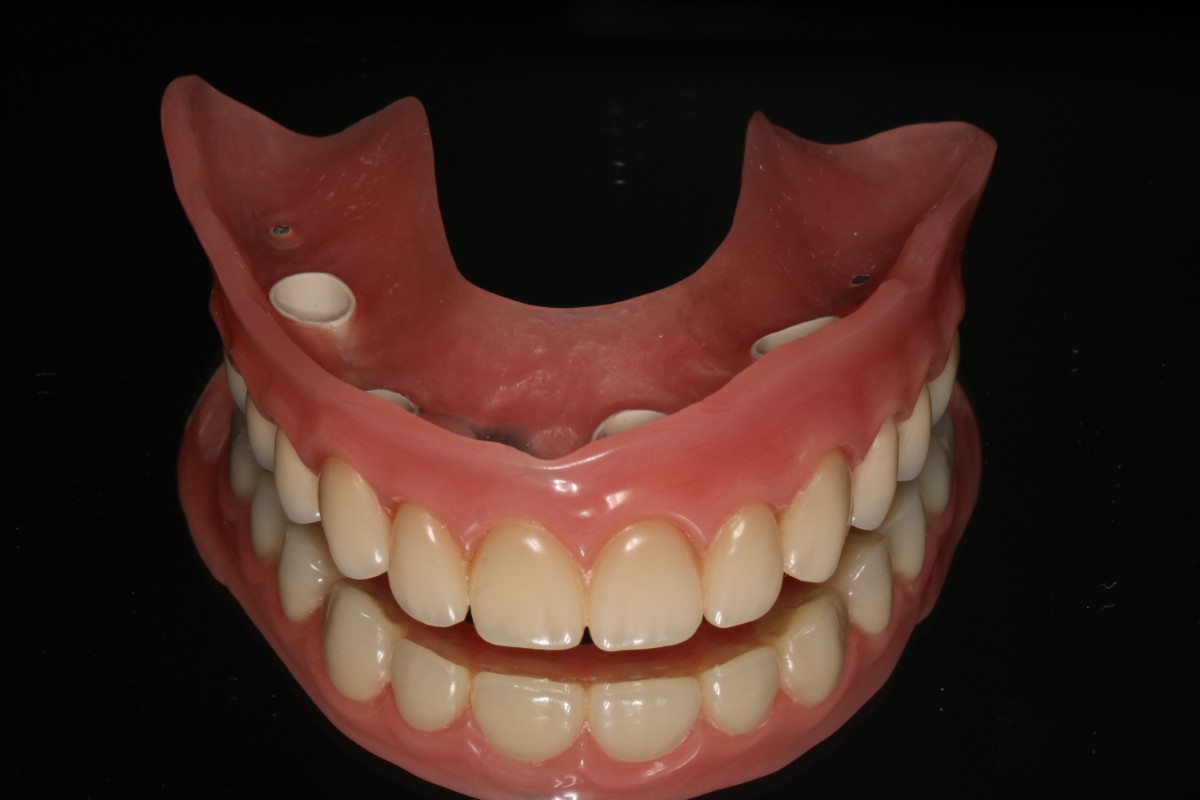

1. Proteza wykonana wg protokołu All On X

Metoda All On X to rewolucyjne podejście do odbudowy całej szczęki na implantach. Polega na osadzeniu pełnej protezy stałej na odpowiedniej liczbie implantów (zwykle 4-6), strategicznie rozmieszczonych w kości szczęki lub żuchwy. Liczba implantów jest dobierana indywidualnie do każdego pacjenta – stąd nazwa “All On X”, gdzie X oznacza optymalną dla danego przypadku liczbę wszczepów.

Proteza wykonana w technice All On X może przez długi okres funkcjonować jako uzupełnienie samodzielne i jest najczęściej wstępem do wykonania stałych uzupełnień protetycznych np. mostów porcelanowych przykręcanych dna implantów

Przypadek 1